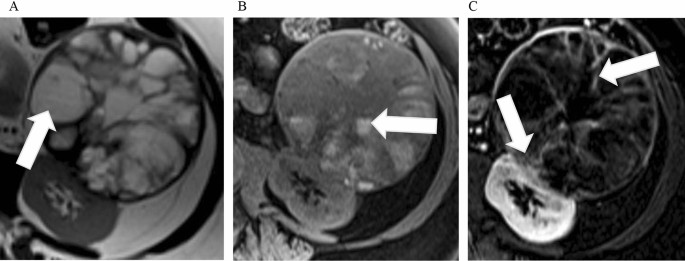

The Vascular Ring Sign In Mesoblastic Nephroma Report Of Two Cases Semantic Scholar